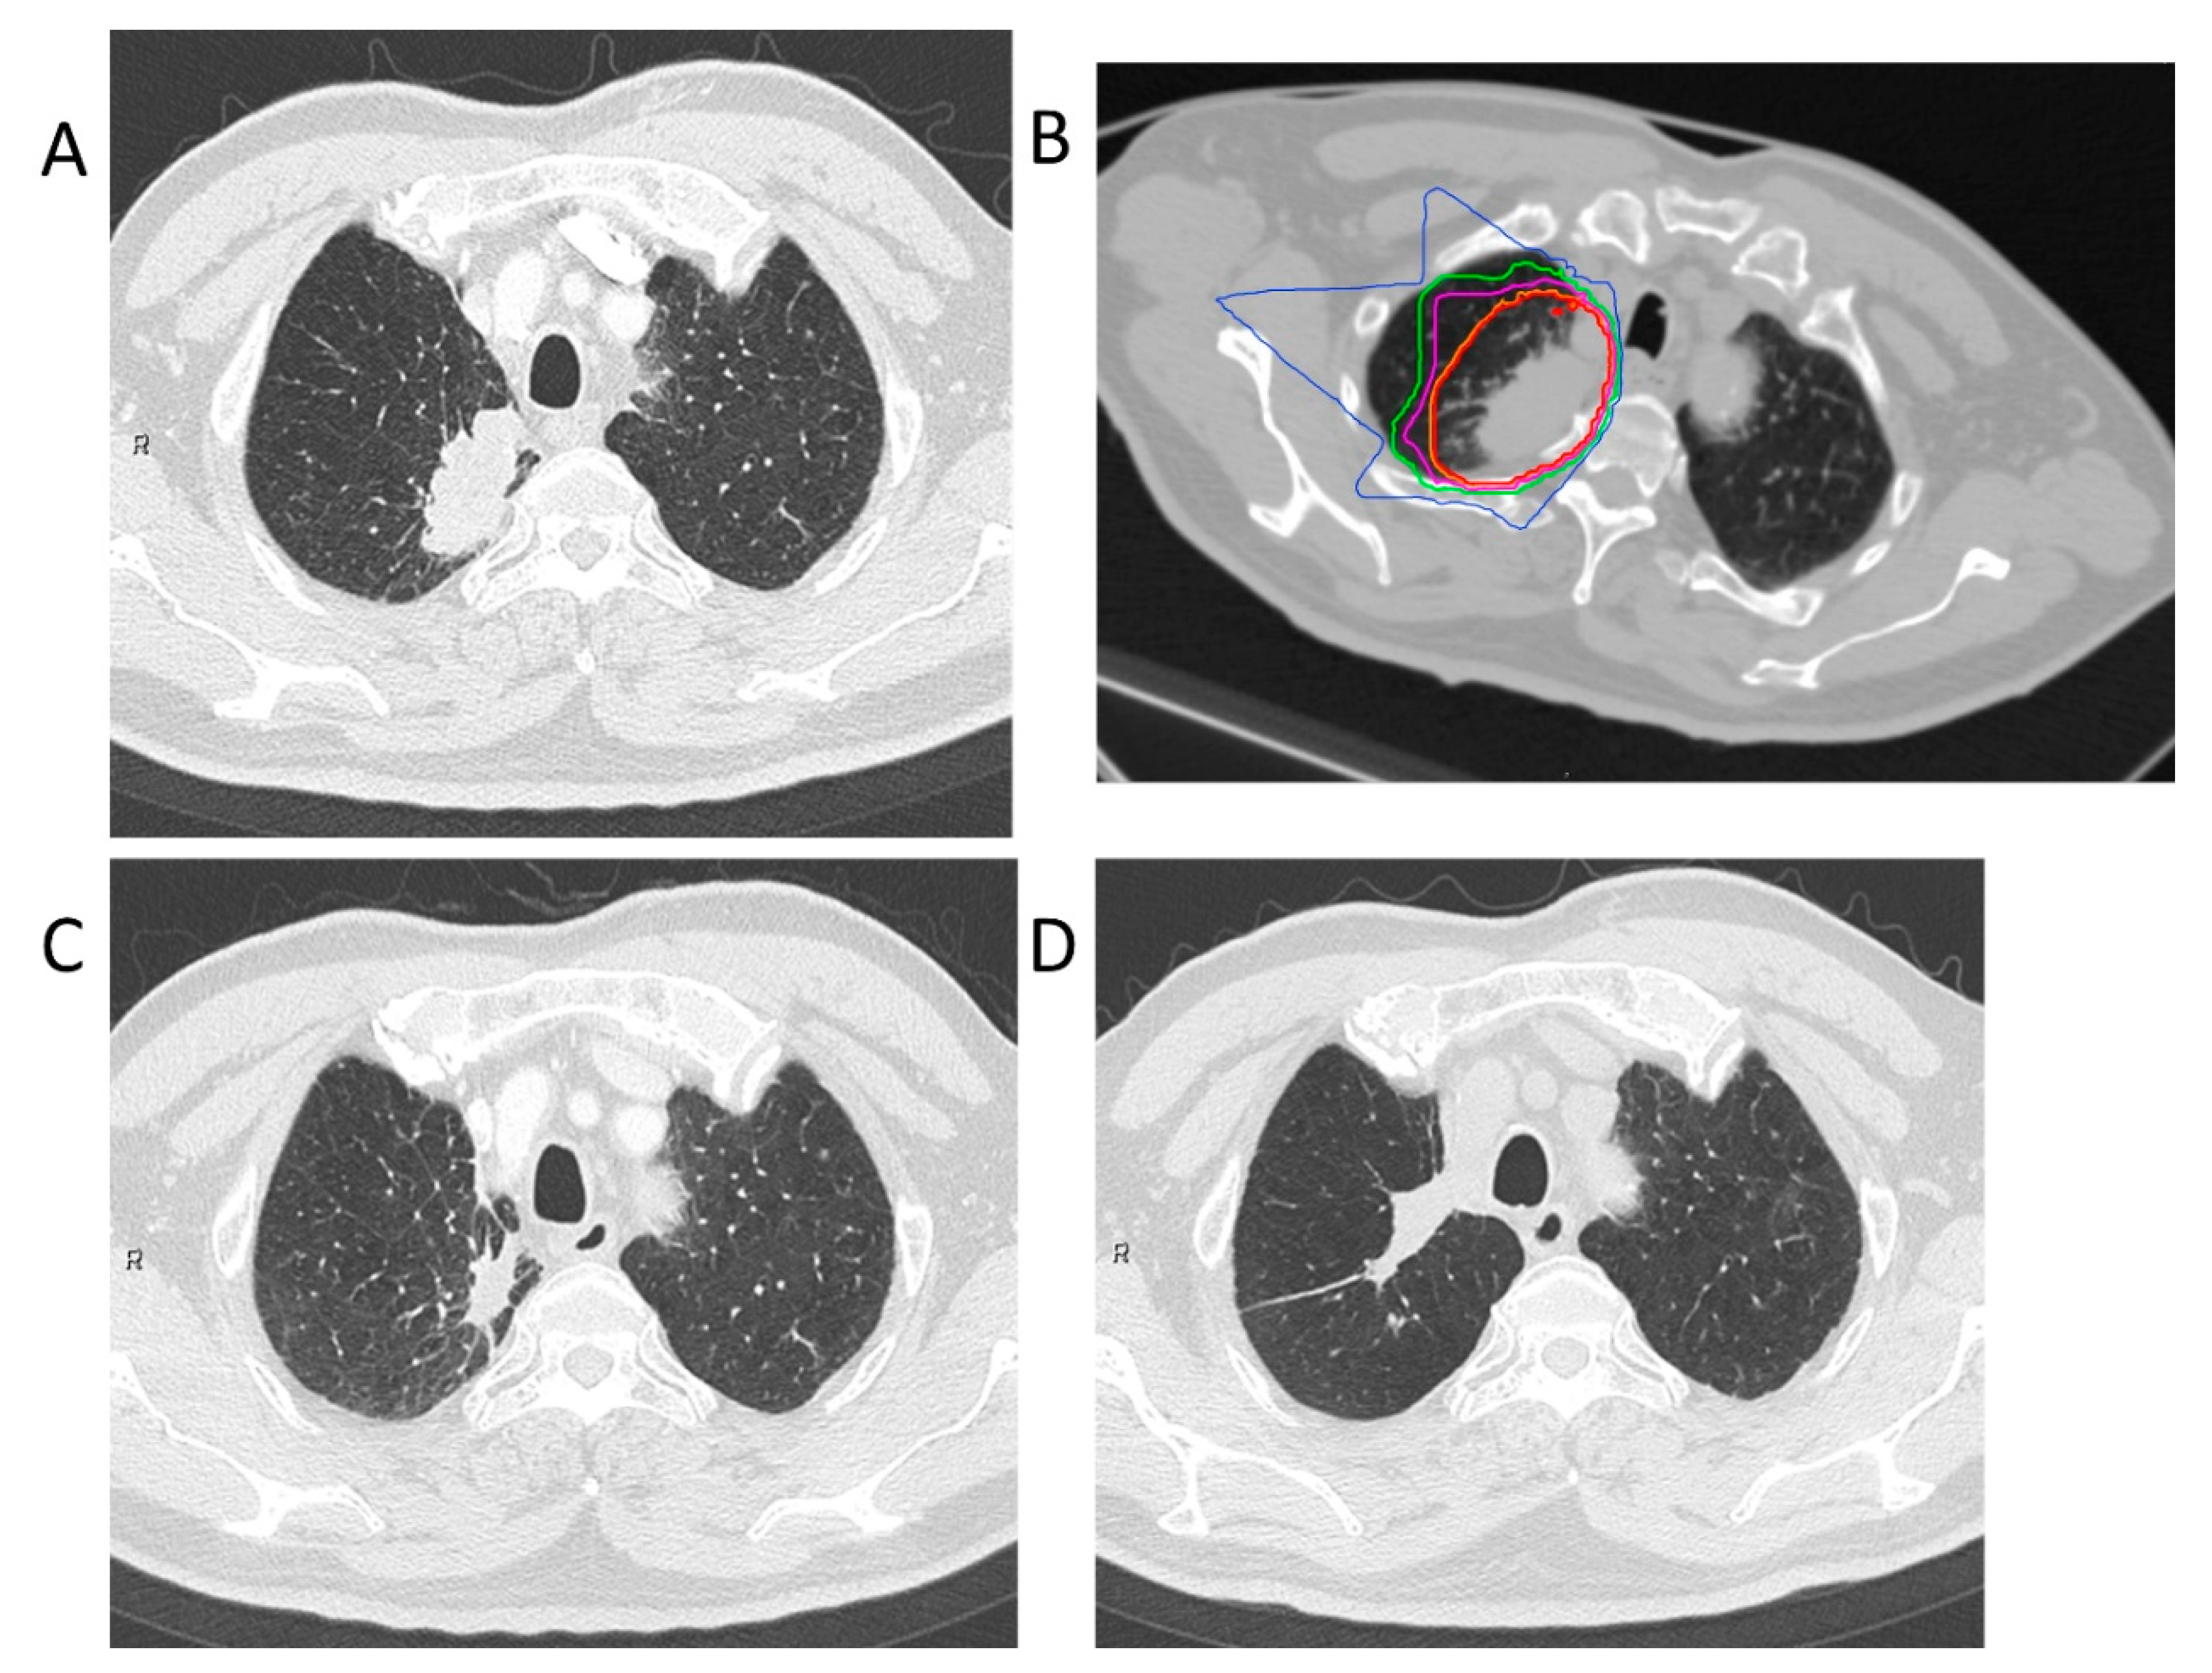

4.2. Carbon-Ion Radiotherapy